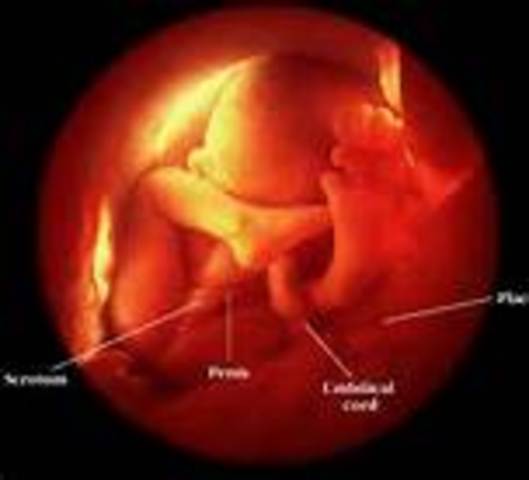

• Week 19

Week 19

I got it fromIf baby is female the uterus starts to develop, the vagina, uterus, and fallopian tubes are in place. Females have a limited supply of eggs in their lifetime. At this point your daughter will have 6 million eggs. This amount decreases to approximately one million by birth. If it's a boy, the genitals are distinct and recognizable. Even if the sex looks obvious, ultrasound operators have been known to make mistakes.